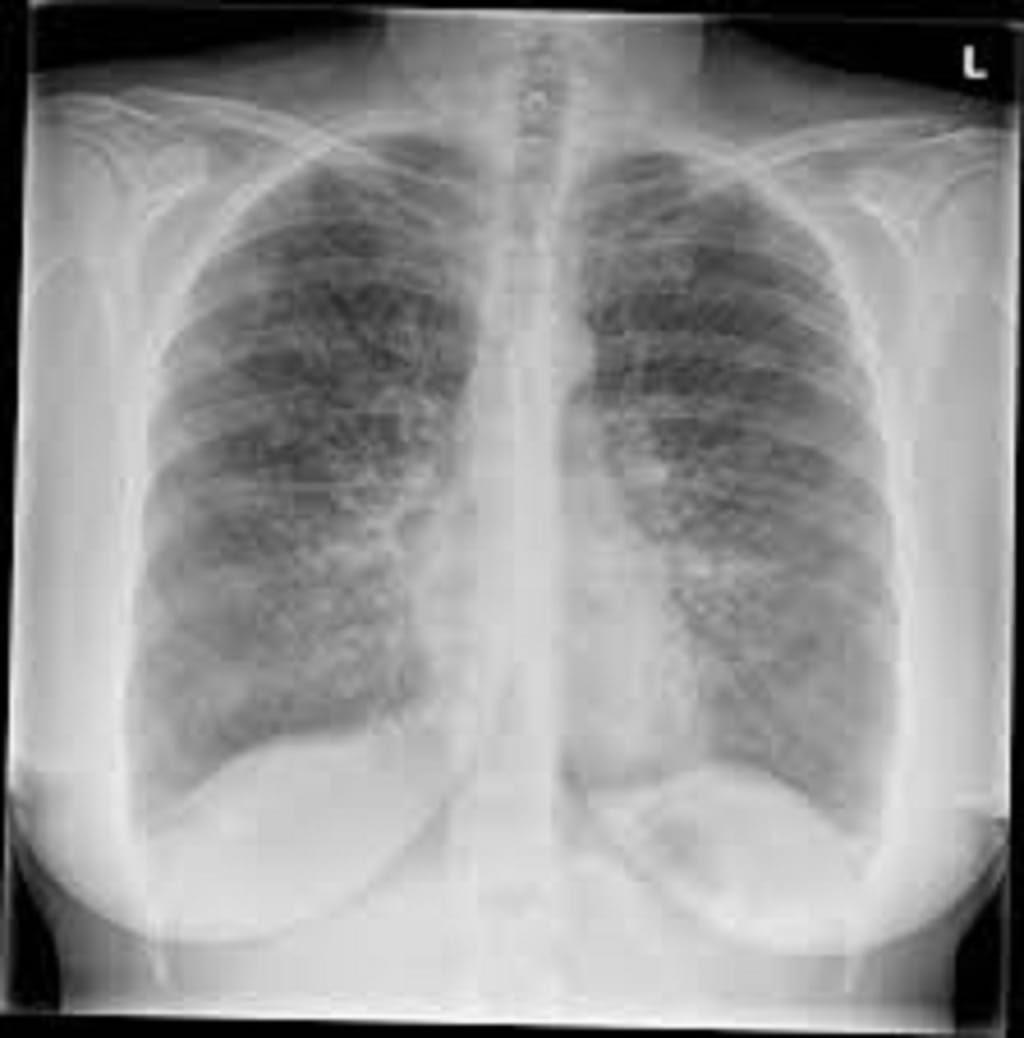

Lymphangioleiomyomatosis (LAM) is a rare lung ailment,caused by mutations in the TSC1 or TSC2 genes which mainly affects women. According to Pfizer Inc., the average age of diagnosis is approximately 35 years.In this disease, abnormal muscle-type cells grow out of control throughout the body especially in the lungs. Over time cysts and clusters of cells might develop in the lungs, averting airflow in or out of lungs, causing severe damage to the healthy lung tissues. Symptoms of lymphangioleiomyomatosis include chest pain, cough, dyspnea, pulmonary infiltrates, restrictive ventilatory defect.